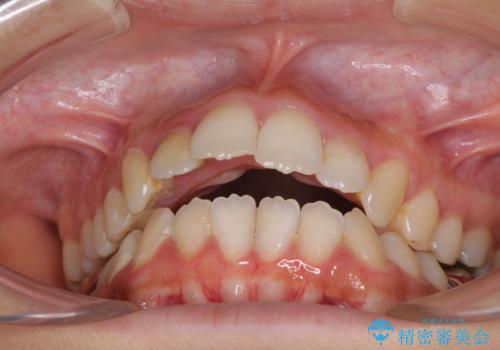

- 口元の突出感と開咬を気にして来院された患者様です。

口元の突出感を改善するため、第一小臼歯を抜歯して口元を引っ込めることとしました。

元々むし歯の処置歯が多く、神経を取り除いている歯が多くありましたが、どうやら右上の前歯と小臼歯は外傷により神経を失った可能性があり、抜歯したスペース前後の歯が全く動かない状態でした。

結果として下顎の小臼歯は抜歯せず、右上の抜歯スペースはむし歯処置を兼ねてオールセラミックブリッジにて補綴治療を行うこととしました。